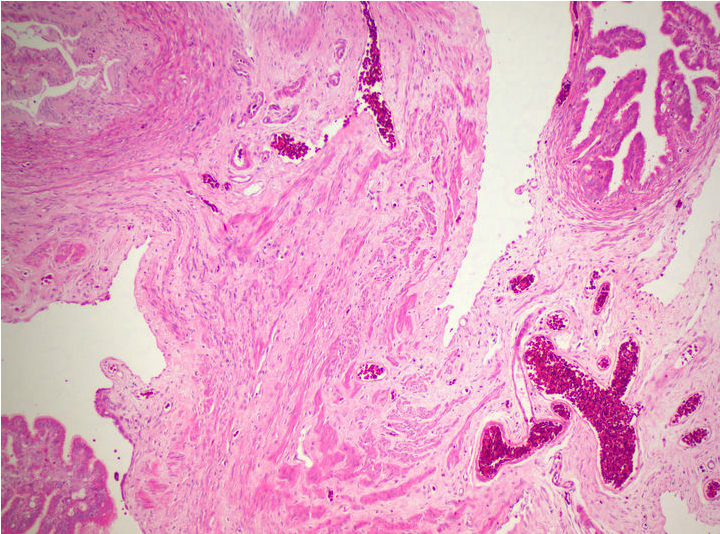

生物显微镜下的卵巢病理切片

病理切片是病理科医生确诊病症的重要工具,观察病理切片一般使用生物显微镜明场观察,一款好的病理切片显微镜,不仅要求使用舒适,还要成像清晰。在生物显微镜ML31的观察下,经过HE染色的卵巢切片呈粉红色,并呈现出丰富而复杂的细节。

卵巢,作为女性生殖系统的重要器官,负责产生卵子和分泌性激素。透过生物显微镜ML31,我们可以看到许多不同种类的细胞。其中较突出的是卵原细胞,这是卵巢中产生卵子的母细胞。在染色切片中,卵原细胞呈现出较大的体积和较深的染色,与其他细胞有所区别。

通过生物显微镜ML31观察卵巢染色切片,我们可以了解卵巢的基本结构和功能。这不仅有助于我们对生殖系统的理解,也为研究卵巢疾病的病因、病理和治疗方法提供了重要依据。